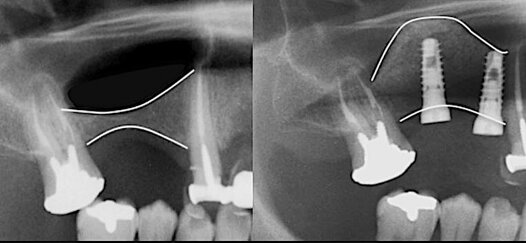

Il rialzo del seno mascellare è un intervento chirurgico necessario per inserire impianti dentali nei settori posteriori del mascellare superiore quando l’osso è insufficiente. Questa tecnica permette di aumentare lo spessore osseo, mediante l’innesto di biomateriali, creando una base stabile per l'inserimento dell' impianto dentale.

La perdita di denti posteriori può causare un progressivo riassorbimento osseo e un abbassamento del seno mascellare, una cavità naturale vuota rivestita da una membrana epiteliale.

Per compensare questa riduzione, si possono adottare due tecniche:

Mini rialzo del seno mascellare per deficit ossei lievi.

Grande rialzo del seno mascellare per riassorbimenti più significativi.

La scelta della tecnica più adatta dipende dall’altezza dell’osso residuo.

RIALZO DEL SENO MASCELLARE